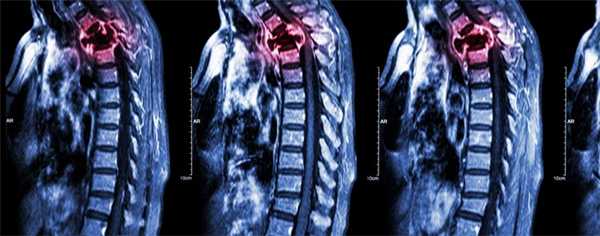

Гинекологический рак является распространенной неоплазией и составляет 10-15% от всех злокачественных новообразований у женщин (1). Задача визуализации до лечения является стадирование злокачественного процесса для дальнейшего планирования терапии и манипуляций. Задача визуализации после лечения (хирургических манипуляций, химиотерапии, лучевой терапии) являются оценка ответа на терапию. Компьютерная томография (КТ) является методом выбора для оценки рецидива рака яичника (2). Магнитно-резонансная томография (МРТ)—в частности, с динамической контрастированием имеет высокую чувствительность (91%) при выявлении рецидивов гинекологического рака (3).

Существуют различные онкологические варианты в гинекологии, в зависимости от локализации, гистологического типа, а также степени и стадии заболевания, поэтому важно, чтобы диагност был готов правильно оценить изображения пациентов после химиотерапии, лучевой терапии или их комбинации, интерпретируя исследование и избегая ошибок в дифференциации нормальной анатомии после лечения и рецидива заболевания.

Химиотерапия чаще используется в качестве неоадъювантного лечения при высокодифференцируемом раке яичников, реже высокодифференцируемом раке шейки матки. Адъювантная химиотерапия используется после операции по поводу рака яичников и рака эндометрия. Первичные химиотерапия и лучевая терапия применяется для лечения распространенного рака шейки матки (2-4 стадии) (4). При эндометриальной карциноме лучевая терапия применяется после хирургического вмешательства у пациентов, у которых патологический процесс распространяется на миометрий или выходит за пределы матки. При раке яичников лучевая терапия рекомендуется только в качестве паллиативного лечения при IV стадии заболевания (4,5).